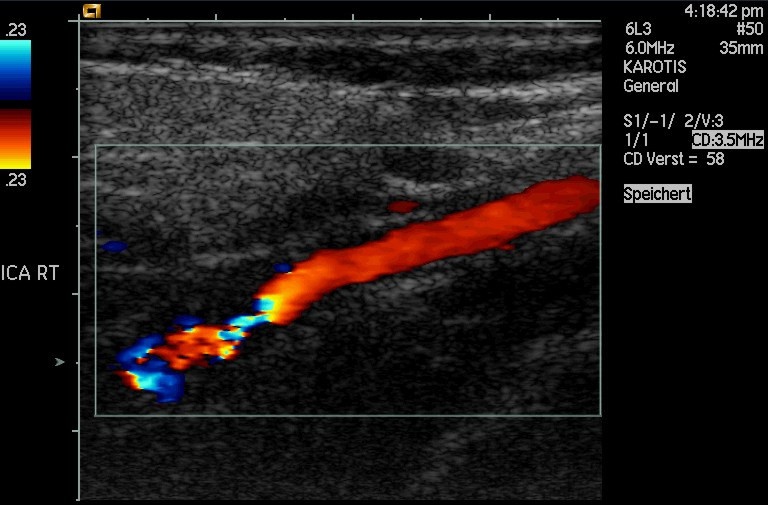

Another major use of ultrasound in medical diagnostics is to detect motion and determine velocity through the Doppler shift of an echo, known as Doppler-shifted ultrasound. This technique is used to monitor fetal heartbeat, measure blood velocity, and detect occlusions in blood vessels, for example. (See this figure.) The magnitude of the Doppler shift in an echo is directly proportional to the velocity of whatever reflects the sound. Because an echo is involved, there is actually a double shift. The first occurs because the reflector (say a fetal heart) is a moving observer and receives a Doppler-shifted frequency. The reflector then acts as a moving source, producing a second Doppler shift.